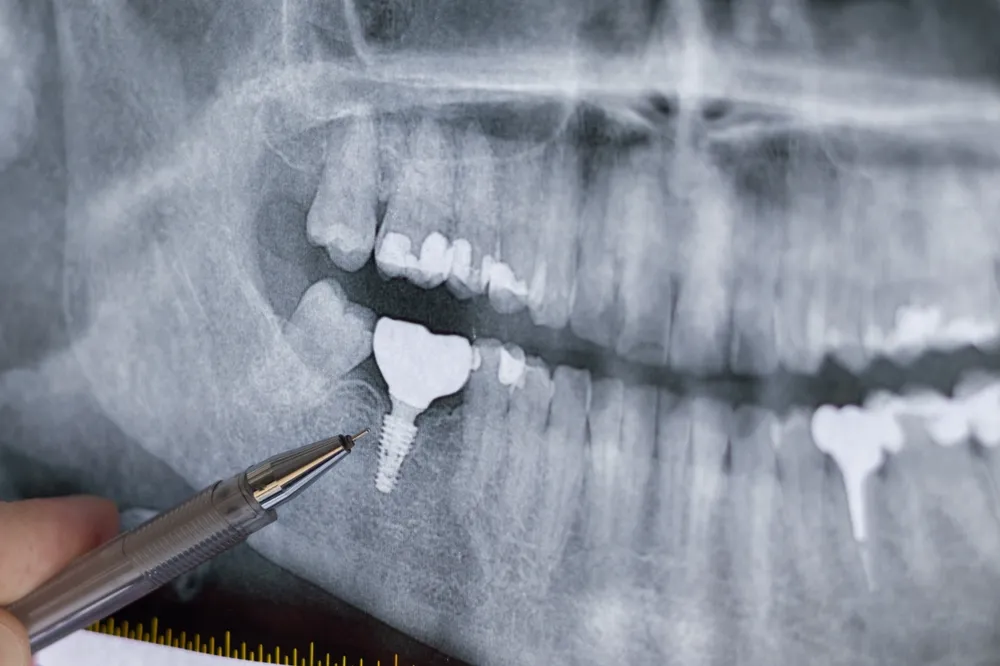

インプラント治療は、顎の骨に人工の歯根を埋め込み、その上に人工歯を装着する方法です。顎の骨に固定されるため装置が動きにくく、隣の歯に頼らず独立して機能するため健康な歯への負担を抑えやすい点が特徴です。

見た目と機能の両方を重視したい場合に検討されることが多い方法ですが、外科処置を伴うため顎の骨の量や全身の健康状態を確認しながら進める必要があります。

インプラントの大きなメリットは、しっかり噛みやすいことです。顎の骨に固定されるため装置が動きにくく、硬さのある食べ物でも力を入れやすくなります。また独立した構造で機能するため周囲の歯を削らずに治療できるケースが多く、健康な歯への余分な負担を抑えられる点も強みです。

顎の骨に刺激が伝わりやすいため骨の変化を抑える一助となる可能性もあり、長期的な安定を重視する方にとって検討しやすい方法です。

インプラントは外科処置を伴うため、全身の健康状態や顎の骨の量を確認しながら進める必要があります。骨の状態によっては追加の処置が必要になる場合もあるため、事前の診査が重要です。

また骨と結合するまでに一定の期間が必要なため治療完了まで数か月かかることがあります。治療後も定期的なメンテナンスを続けることが安定した状態の維持につながります。